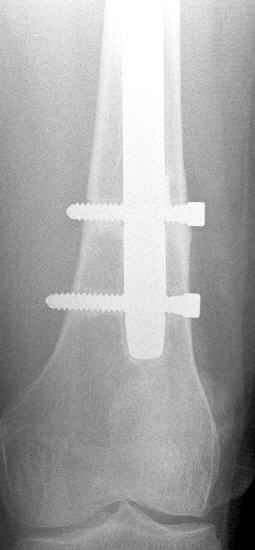

May I have some advice on the following case? Middle aged woman, No chronic medical problems, +tobacco use - but she promises she's going to quit! Original MVC in late 1990's, initial rod failed, and 2 subsequent exchanges failed (most recently shown in attached jpgs.)

Most recent one (6/2002) was apparently an open nailing to remove last broken nail, but no grafting was performed in conjunction. Now sent to me with broken 14mm R/T nail in place. WBC, Hgb, Chemistries normal. ESR 34 CRP 4.2 No other apparent locus of infection. I was considering a staged approach - removing nail and screws and obtaining cultures. If negative, proceed with exchange nailing with open grafting +/- BMP, But how best to deal with that pedestal distally and avoid anterior breech near patella? If positive cultures, what would be best option? Thanks. Tom Schaller Kalamazoo, MI.